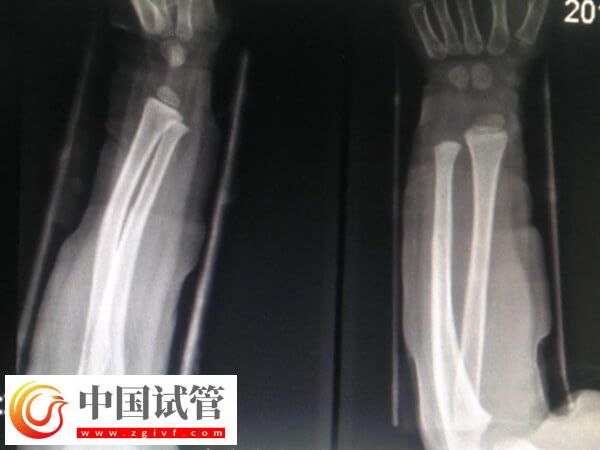

骨折愈合一年可不可以做試管

患者骨折愈合一年之后一般是可以做試管嬰兒的,這時(shí)骨折部位已經(jīng)基本恢復(fù)穩(wěn)定,身體也基本恢復(fù)到正常狀態(tài),所以不會(huì)對(duì)試管嬰兒的整個(gè)流程產(chǎn)生直接的不良影響。不過(guò)為了確保妊娠的安全性,建議患者一定要注意觀察身體狀態(tài),以及骨折位置,若是有任何異常,則建議及時(shí)就醫(yī),以提高試管妊娠成功率。

骨折過(guò)的人,多數(shù)能夠恢復(fù)到原來(lái)正常水平一樣。因?yàn)榇蠖鄶?shù)的骨折都可以得到及時(shí)的正確的復(fù)位,都能恢復(fù)到原來(lái)正常水平一樣。所以骨折愈合一年后是可以做試管嬰兒的,但為了確保骨折位置和妊娠的安全性,建議患者還要注意以下幾點(diǎn)事項(xiàng)。